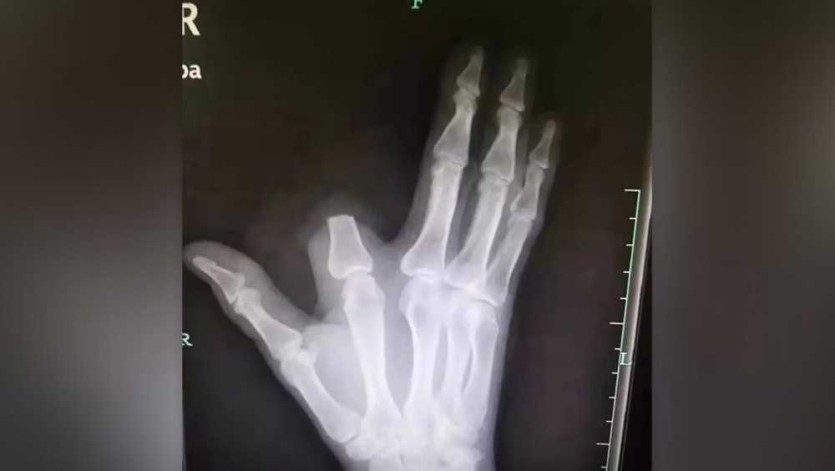

중국 저장성에 거주하는 60세 농부 장씨는 산에서 작업을 하던 중 독사에게 손가락을 물렸습니다.

그는 이 뱀이 물리면 다섯 걸음 안에 죽는다는 전설의 '오보사'라고 판단하고, 독이 퍼지는 것을 막기 위해 자신의 검지 손가락을 즉시 절단했습니다.

이후 그는 절단된 부위를 천으로 감싸고 80km 떨어진 항저우 시내 병원을 찾아갔습니다.

병원에 도착한 장 씨를 진찰한 의사들은 "손가락을 자를 필요가 전혀 없었다"고 말했습니다.

그가 물린 뱀은 독성이 있긴 하지만, 전설처럼 즉사할 정도의 치명적인 독은 아니었기 때문입니다.

장 씨는 병원 도착 당시 호흡 곤란이나 출혈 등 심각한 중독 증상을 보이지 않았으며, 상태가 매우 양호했습니다.

장 씨는 급하게 병원을 오느라 잘라낸 손가락을 산에 그대로 두고 왔습니다.

이 때문에 의료진은 그의 손가락을 다시 붙여줄 수 없었습니다.